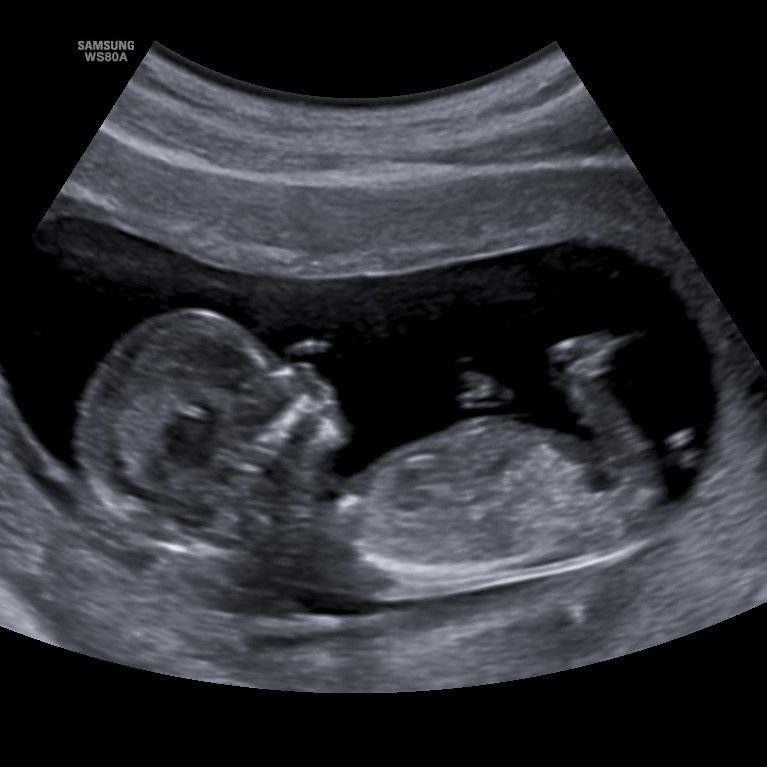

Pränataldiagnostik und Schwangerschafts-betreuung

Die Betreuung vor und während einer Schwangerschaft ist für die Gesundheit von Mutter und Kind essentiell. Insbesondere die Überwachung der fetalen Entwicklung ist von großer Bedeutung.

Insbesondere wenn es um die Gesundheit des ungeborenen Kindes geht, spielt die Pränataldiagnostik eine entscheidene Rolle. Durch moderne Verfahren wie die NT-Messung (Nackenfaltenmessung) und dem fetalen Herzecho können Ärzte frühzeitig Anomalien erkennen und somit präventive Maßnahmen ergreifen. Ultraschalluntersuchungen bieten zudem wertvolle Einblicke in die Entwicklung des Fötus und ermöglichen es, potenzielle Risiken frühzeitig zu identifizieren. Diese diagnostischen Möglichkeiten tragen nicht nur zur Sicherheit des ungeborenen Kindes bei, sondern stärken auch das Vertrauen der werdenden Eltern.